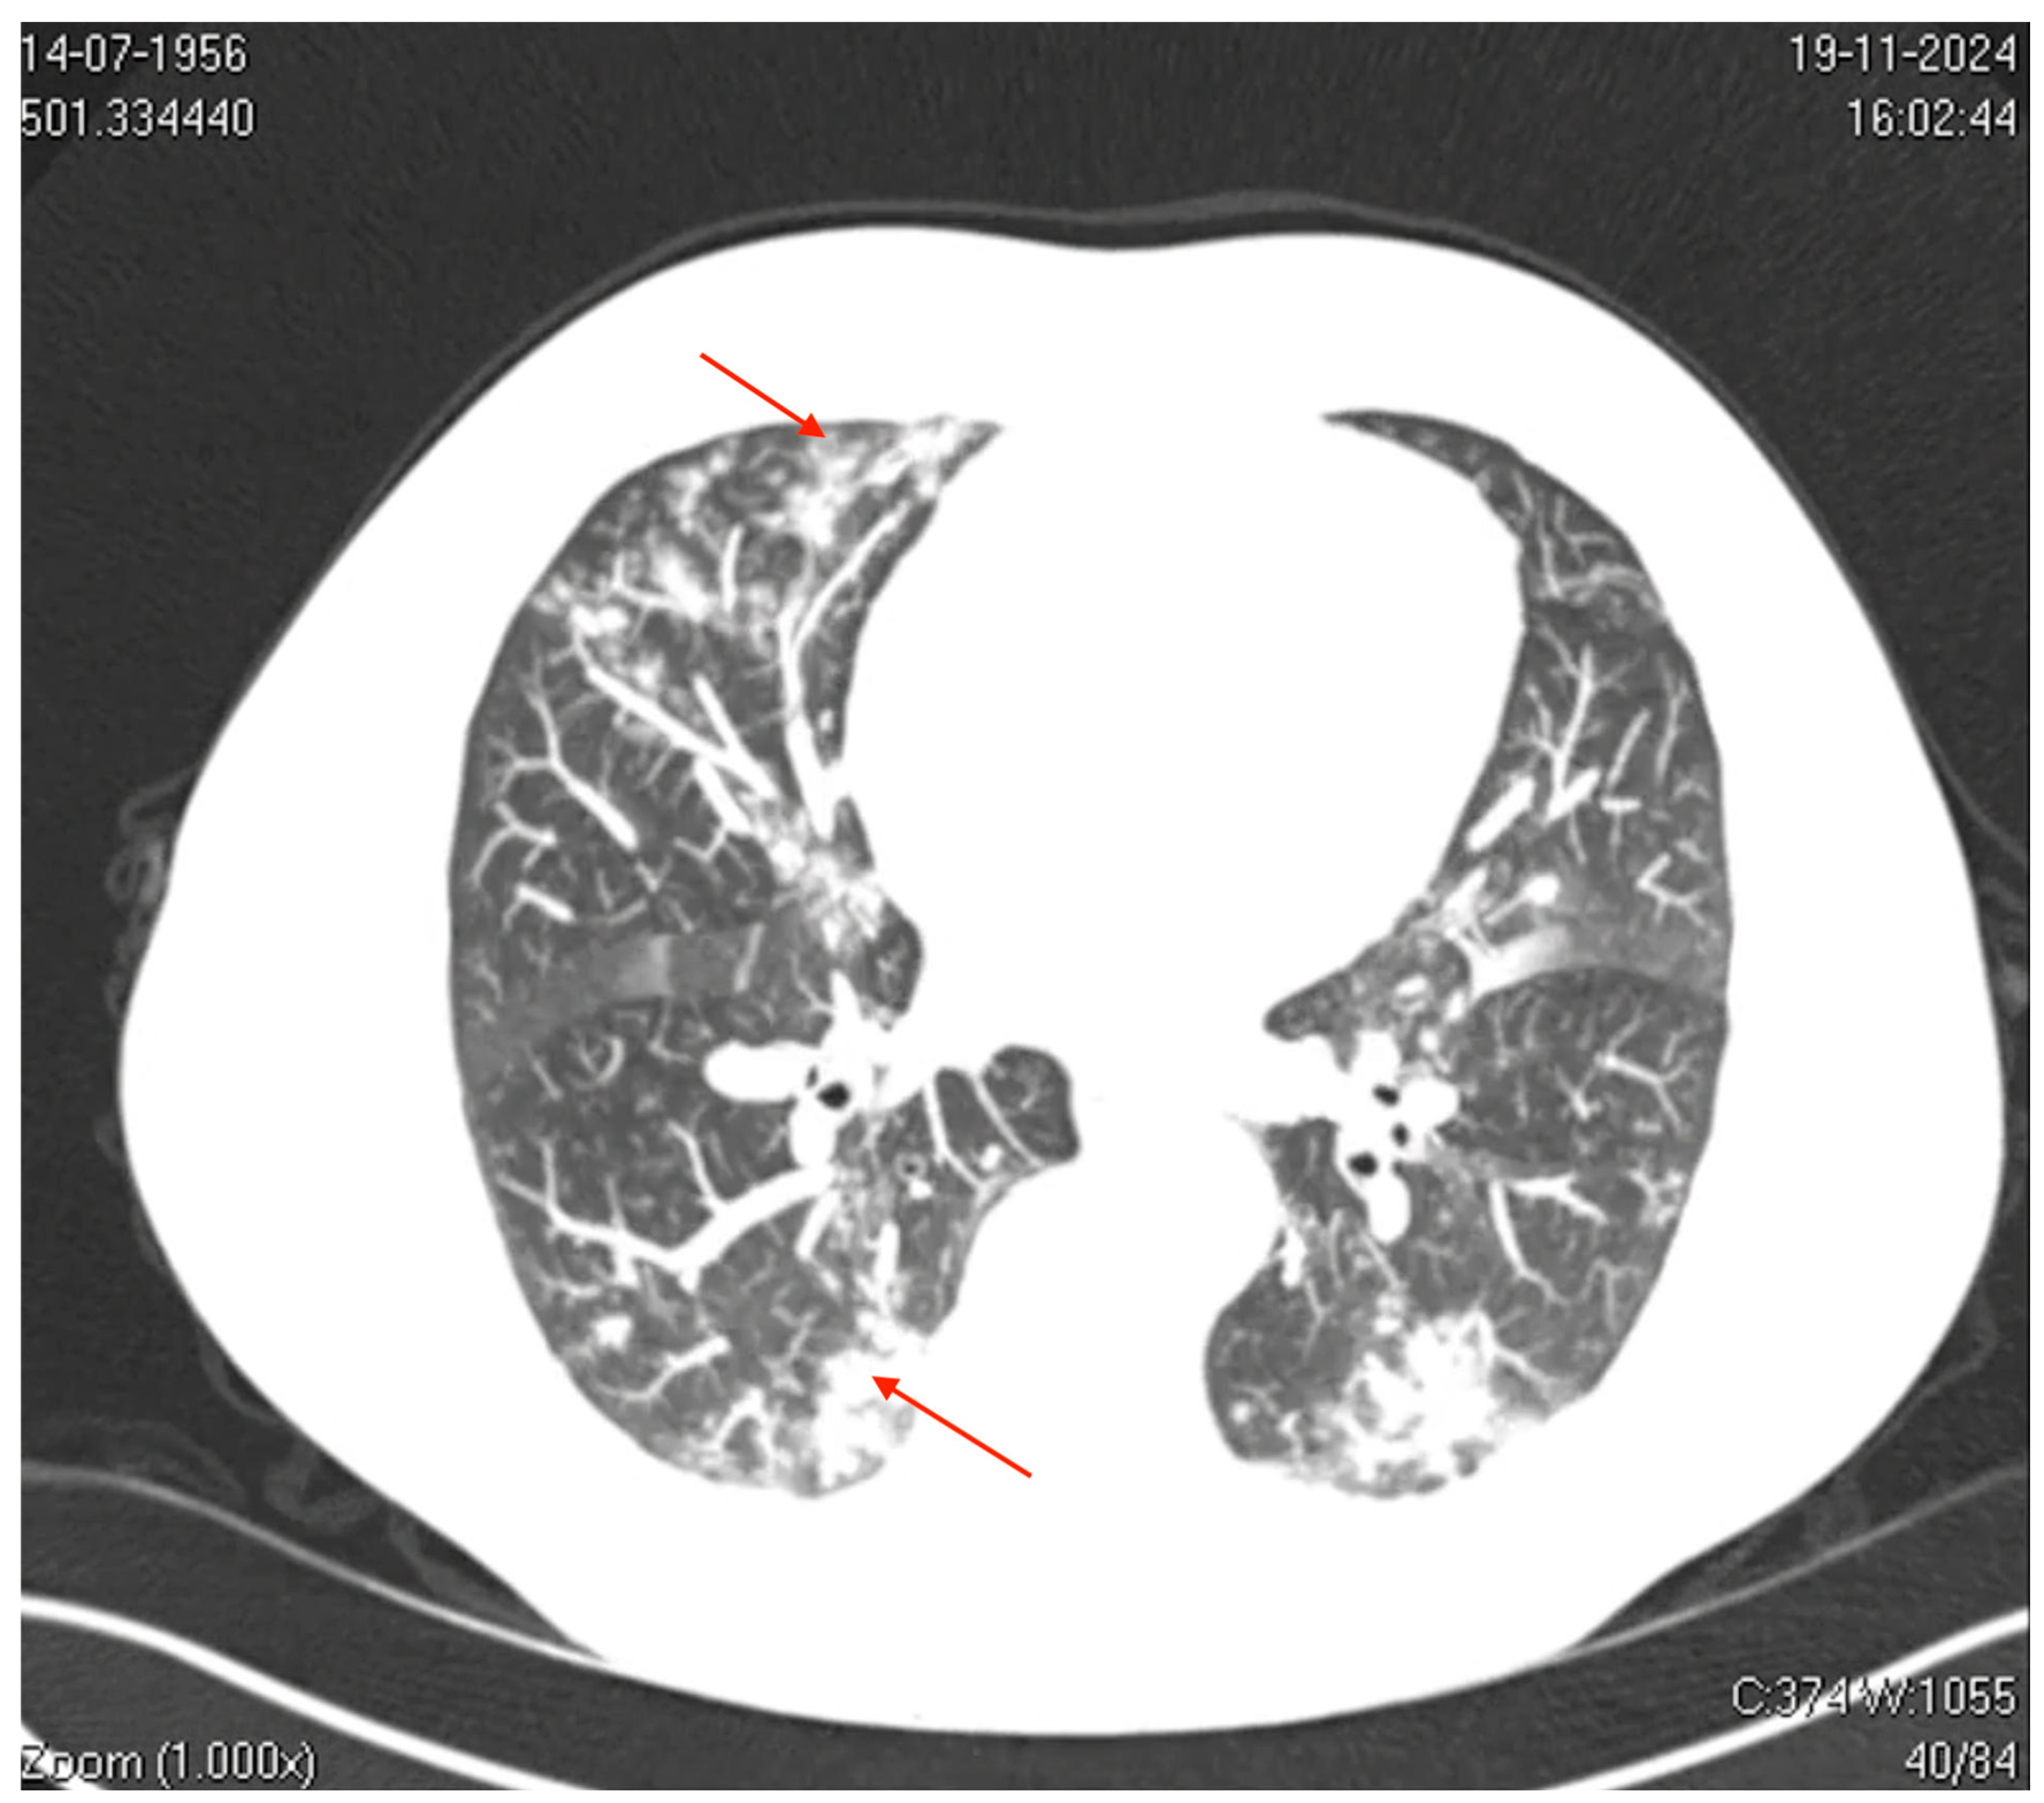

Figure 2.

Axial computed tomography (CT) image of the thorax. The image shows bilateral ground-glass opacities with a reticular pattern interspersed with focal areas of consolidation and peripheral bronchiolar filling. The red arrows highlight specific areas of consolidation surrounded by ground-glass opacities, which are more prominent in the peripheral and lower lung regions. These findings suggest a diffuse inflammatory or infectious process involving the pulmonary interstitial and peripheral airways (acinus and bronchioles), which is consistent with viral pneumonia.

Axial computed tomography (CT) of the thorax revealed mild bilateral pleural effusions, small centrilobular opacities with multilobar distribution, and ground-glass opacities, some of which were coalescent and interspersed with areas of consolidation. These findings predominantly affected the left upper and lower lobes, involving the pulmonary interstitium and peripheral airways (acinus and bronchioles), which is consistent with a viral pneumonia pattern.

The radiological findings, characterized by diffuse ground-glass opacities and consolidations predominantly in the lower lobes, are consistent with the typical imaging pattern observed in viral pneumonia [21]. These radiological features overlap with those observed in other viral infections, such as SARS-CoV-2 and RSV, complicating diagnostic differentiation. However, the absence of bacterial consolidation patterns and low procalcitonin levels substantiated a viral etiology without bacterial superinfection [2]. This case highlights the importance of integrating radiological, clinical, and molecular data for accurate diagnostic assessment during seasonal respiratory surges.